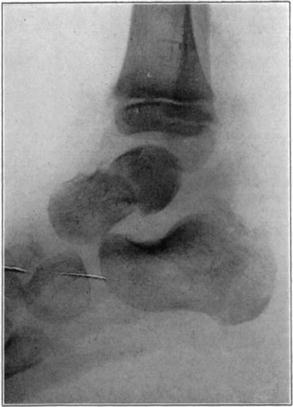

Necrosis of Os Calcis

In fracture of the neck of the os calcis the body may rarely have so much of its blood supply cut off that it undergoes extensive necrosis. Its subsequent history is analagous to that of a necrotic proximal fragment in intracapsular fracture of the neck of the femur. If bony union between the fragments follows, the necrotic body will be invaded gradually by blood vessels, fibrous, osteogenic, and myelogenous tissue, and a gradual replacement of the necrotic by living elements will be brought about. The replacement may be incomplete and the necrotic portion located farthest from the fracture may be broken down by weight-bearing before the ingrowing tissue reaches it, thereby leading to deformity and permanent derangement of the bone.

The following cases are illustrative of this condition.

Case 2. Seventy-four days after fracture of neck of astragalus, posterior dislocation of body, and reduction by operation. Body necrotic and retained normal density. Atrophy of disuse of other bones. Bony union of fracture.

Case 2. One hundred and sixty days after fracture. Body slightly reduced in density near fracture due to invasion from neck.

Case 3. Fresh fracture of neck of astragalus and chip off superior and posterior portion of os calcis.

Case 3. Two hundred and seventy-four days after injury. Fracture of astragalus united. Superior and posterior part of body broken down and irregular while remaining portion dense and transformed. Indicative of necrosis of body with secondary changes.

Case 3. Eighteen months after injury, showing a defective but gradually reforming articular portion of the body of the astragalus.

The blood supply of the astragalus is derived mainly from a branch of the arteria dorsalis pedis which traverses the sinus tarsi lateral to the neck and breaks up to enter the bone near the junction of the neck and body along the lateral and inferior surfaces. There are very small branches entering the bone mesially and posteriorly at points of ligamentous and capsular attachments. Apparently when there is a fracture along the junction of body and neck the important vessels to the body are interrupted and there may be insufficient circulation through the remaining vessels, so that aseptic necrosis of a large part or all of the fragment follows. It is evident from the partial collapse which occurred in Case 3 that when necrosis of the body is diagnosed, the limb should be protected from weight-bearing for at least several months,—until union, revascularization, and transformation of necrotic area has been largely brought about. It seems probable that some of the bad results that have been reported in fracture of the neck of the astragalus, either united or ununited, have been due to overlooked aseptic necrosis of the body.